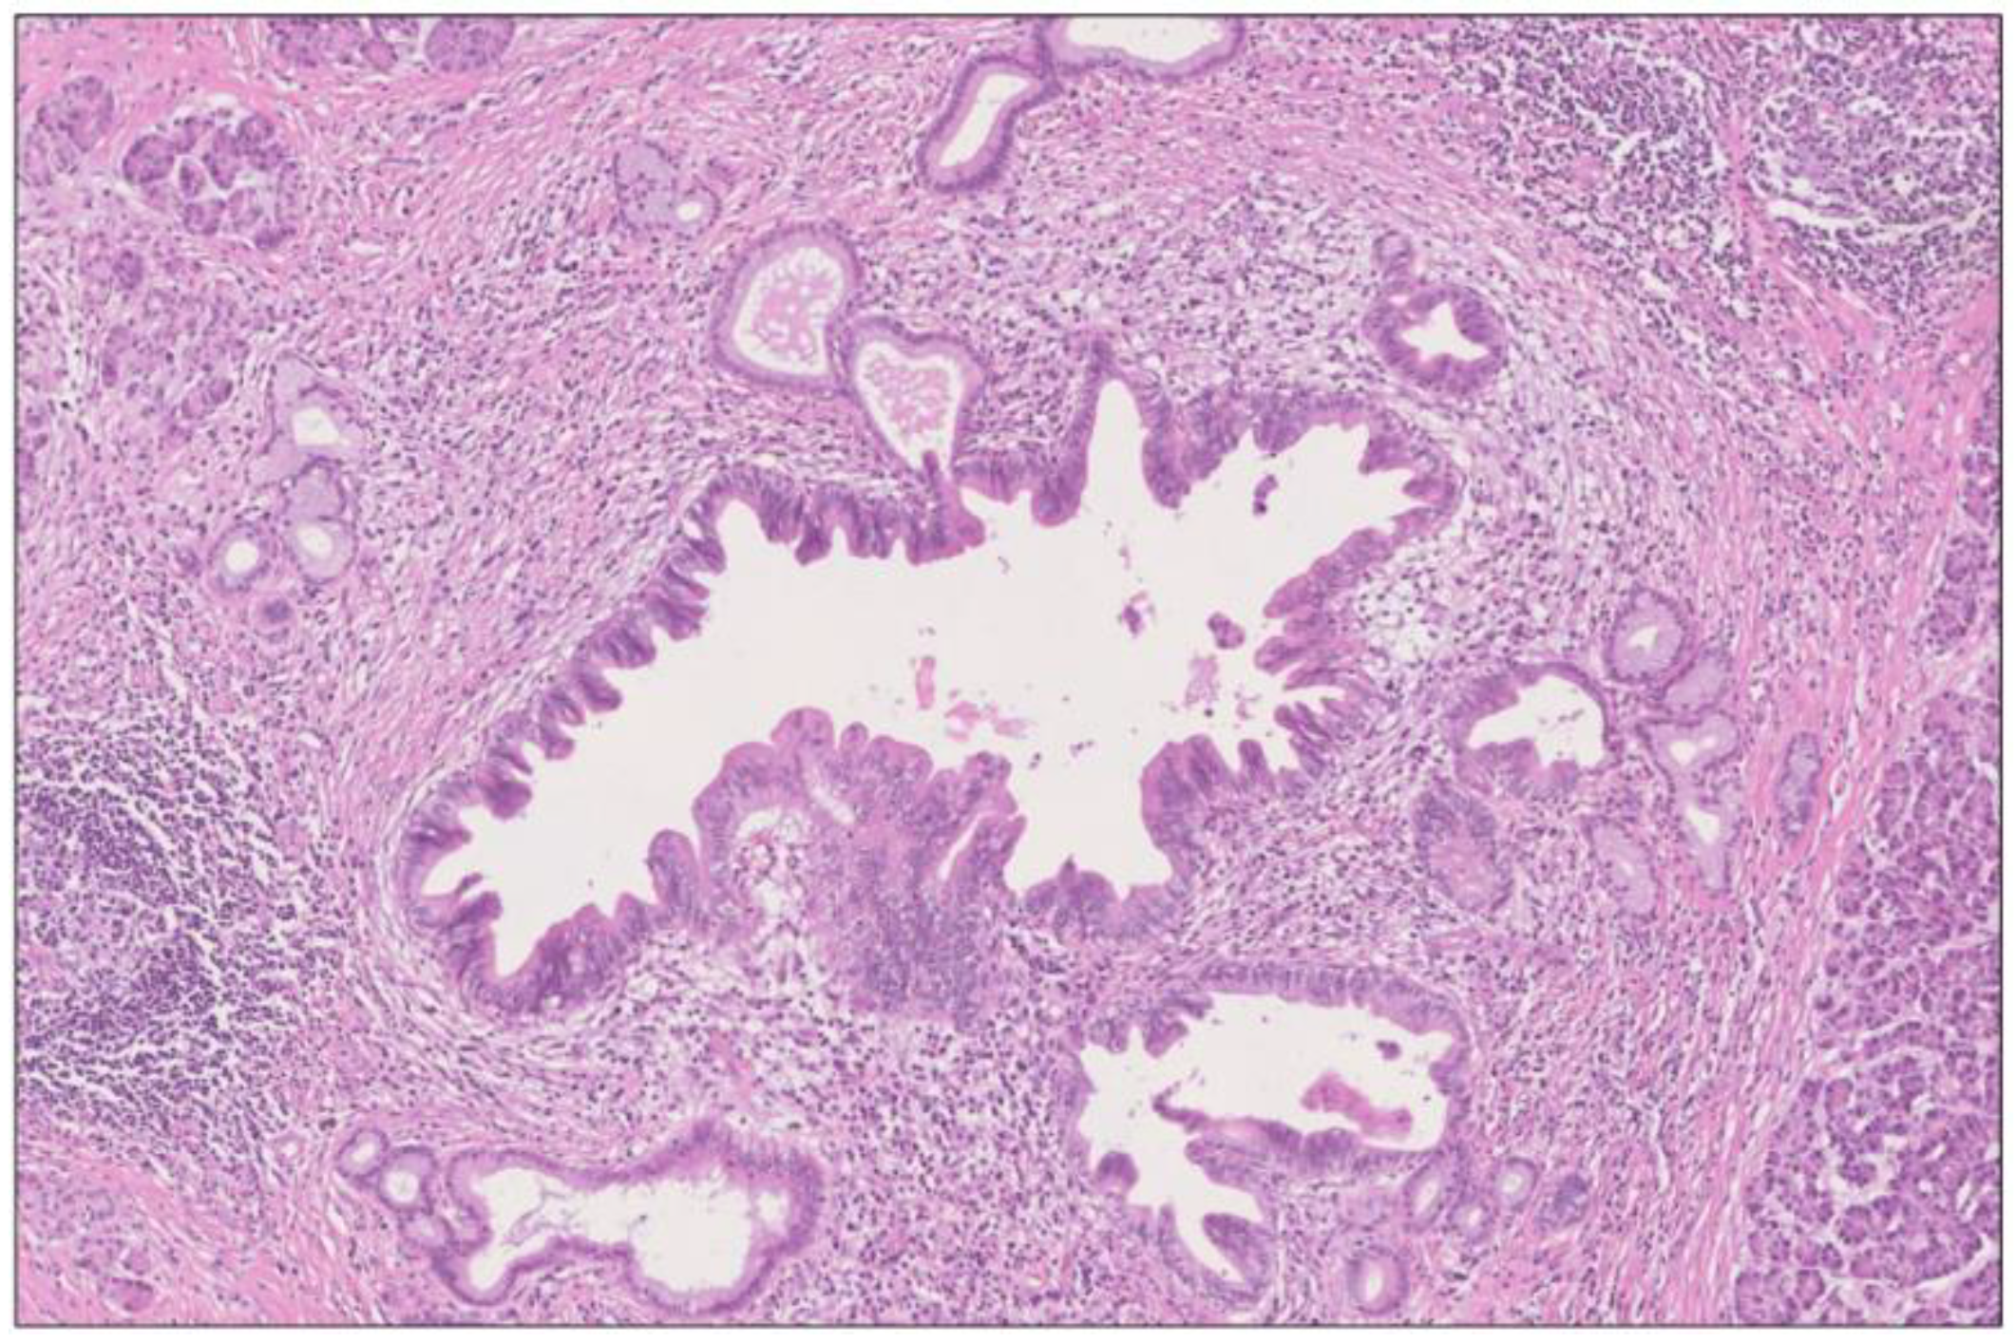

Figure 5. Intraductal papillary mucinous lesion of mixed gastric and intestinal type (immunohistochemistry not shown here) with high-grade dysplasia in main duct (A) and branch duct (B) adjacent to the invasive tumor (C). The lesion has the morphology of an IPMN, although the size (maximum diameter 6 mm) falls in between PanIN and IPMN. H&E staining, 1.5×. The findings correspond to the periphery of the tumor area (A) in Figure 2.